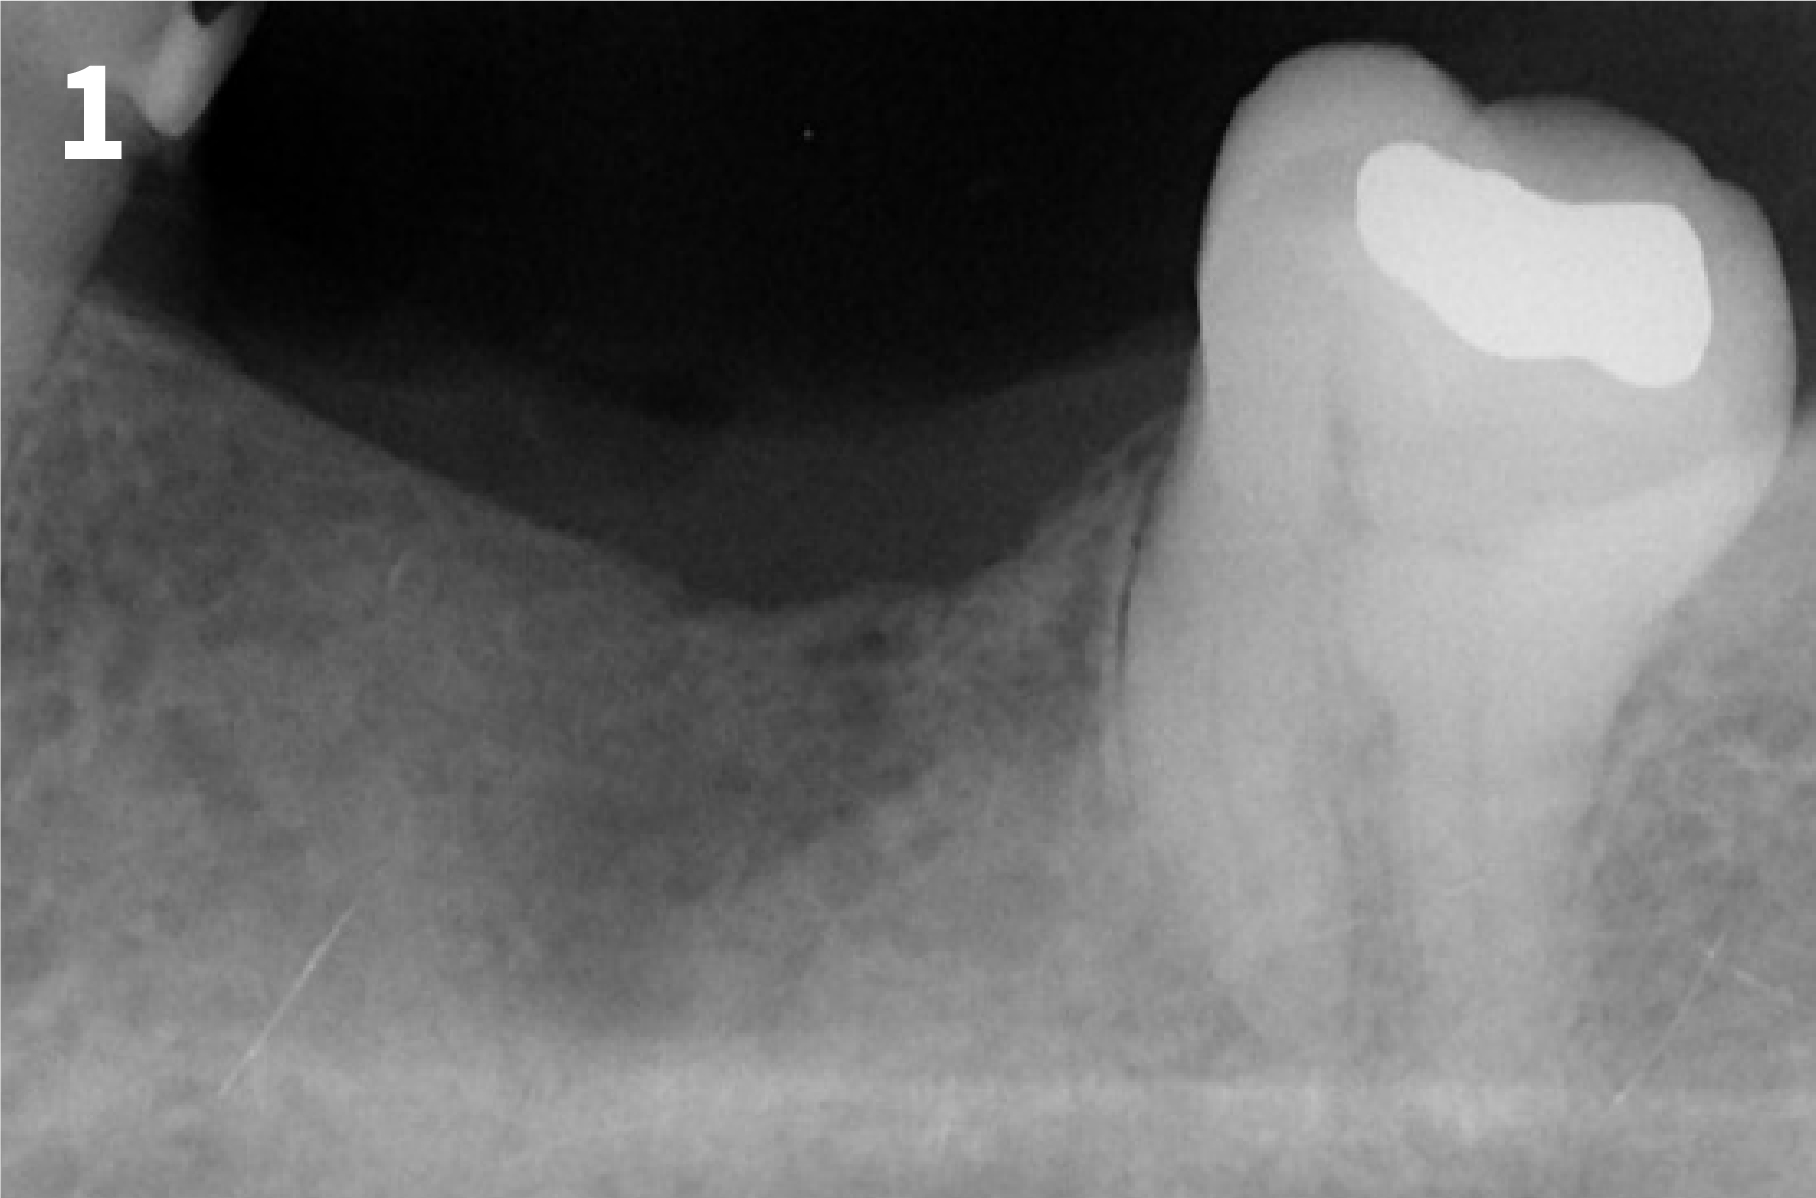

Case 2: Minor Bone Augmentation